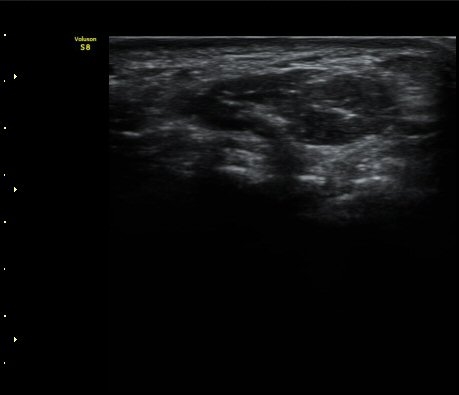

¼ÒÁö±¸ ³»Ãø¿¡ ȾÀ¸·Î ŽÃËÀÚ¸¦ ´ë¾î °¥°í¸®»À °¥°í¸® ³»Ãø¸é ÇÇÁú°ñÀ» °üÂûÇÏ´Ï(¾Æ·¡ ±×¸²)

°¥°í¸® ÇÇÁú°ñ ¿¬¼Ó¼º ¼Ò½Ç(loss of cortical continuity of hook of hamate)ÀÌ °üÂûµÈ´Ù(±×¸² 1, 2).

ÇÇÁú°ñ ¿¬¼Ó¼º ¼Ò½ÇÀº °ÇÃø°ú ºñ±³ÇØ¸é ´õ¿í ¶Ñ·ÈÇÏ´Ù(±×¸² 3, 4).